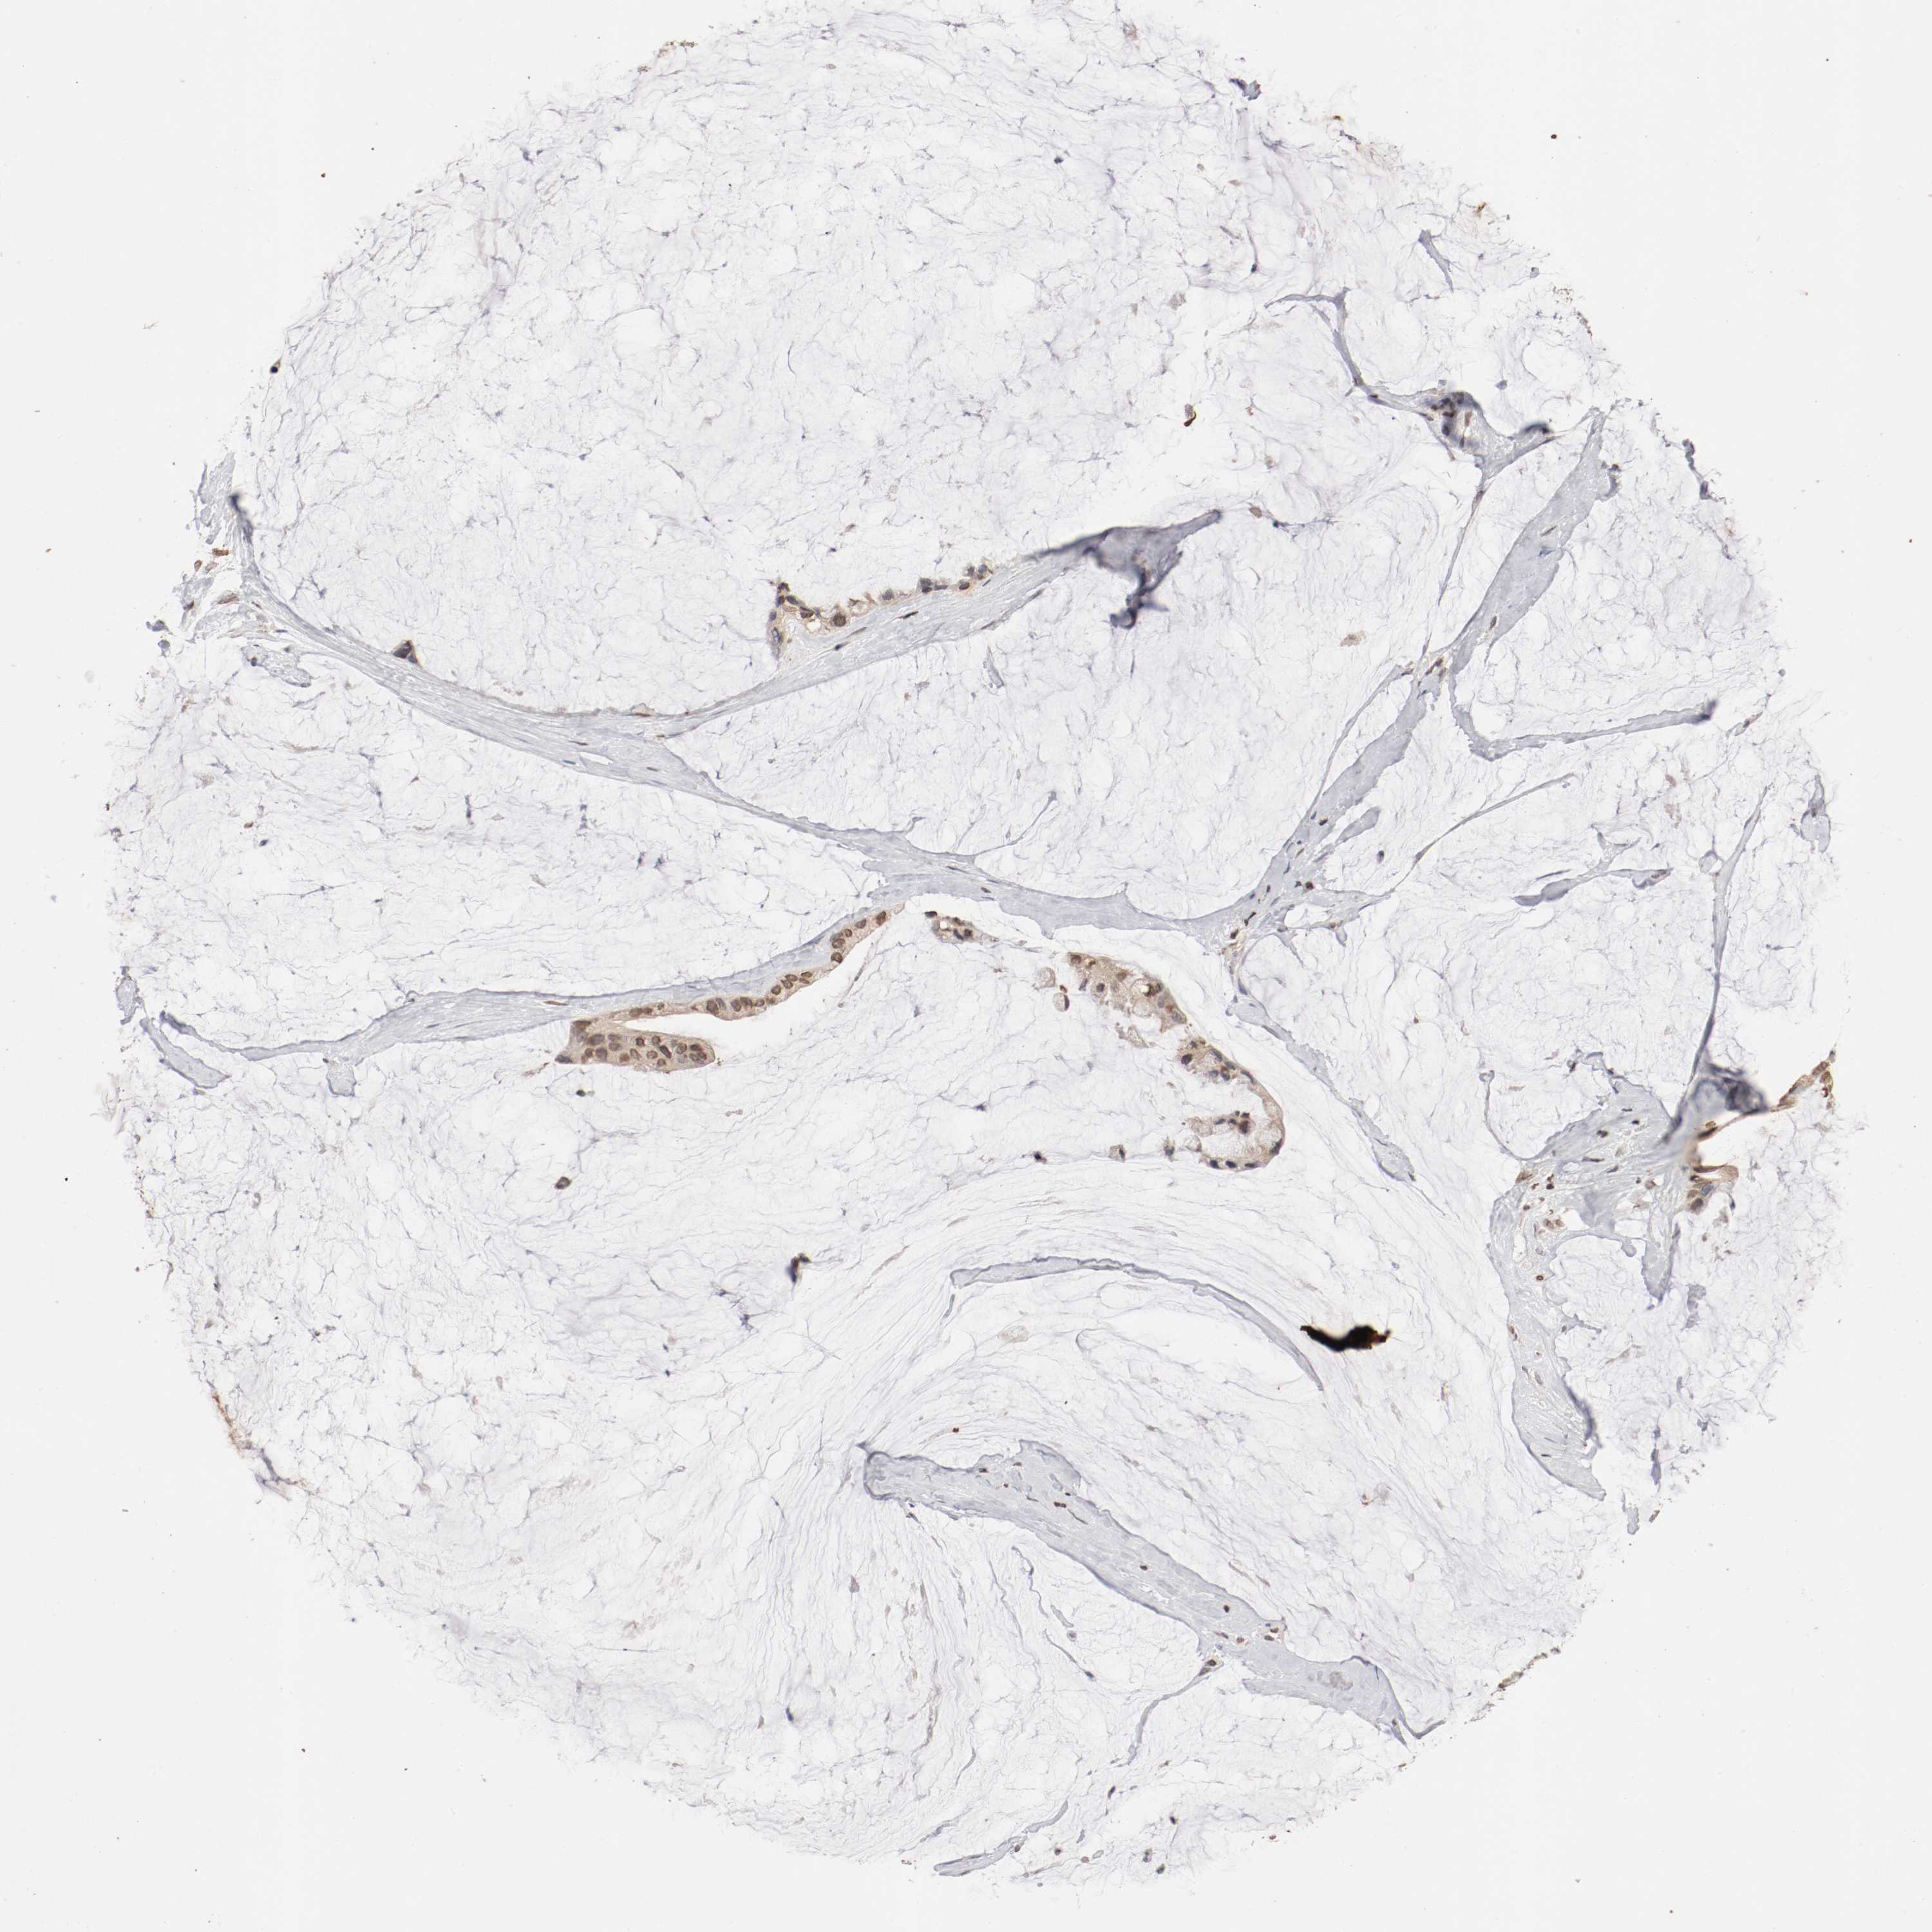

OVARIAN CANCER - Protein expressioni

A mouse-over function shows sample information and annotation data. Click on an image to view it in a full screen mode. Samples can be filtered based on level of antibody staining by selecting one or several of the following categories: high, medium, low and not detected. The assay and annotation is described here.

Note that samples used for immunohistochemistry by the Human Protein Atlas do not correspond to samples in the TCGA dataset.

Antibody stainingi

Antibody staining in the annotated cell types in the current human tissue is reported as not detected, low, medium, or high, based on conventional immunohistochemistry profiling in selected tissues. This score is based on the combination of the staining intensity and fraction of stained cells.

Each image is clickable and will lead to virtual microscopy that enables deeper exploration of all samples and also displays staining intensity scores, fraction scores and subcellular localization as well as patient and tissue information for each sample.

Antibody HPA005750

Antibody CAB005399

Cystadenocarcinoma, mucinous, NOS